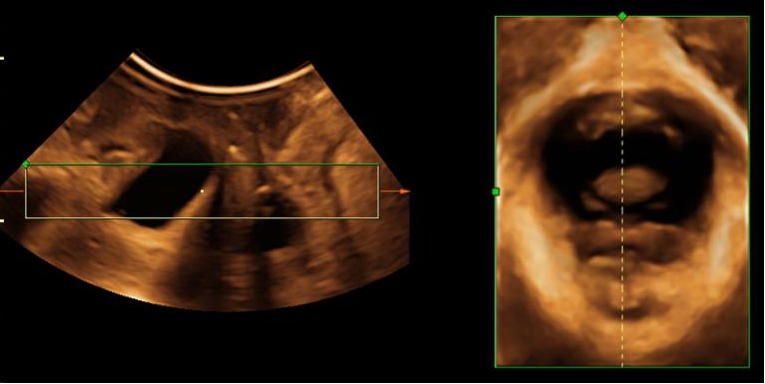

盆底超聲多于會陰部檢查,探頭不需進入陰道內。超聲可觀察盆腔臟器的位置,壓力狀態下臟器位置和形態的變化以及盆底肌損傷情況等。

盆腔臟器脫垂合并肛提肌裂孔增大